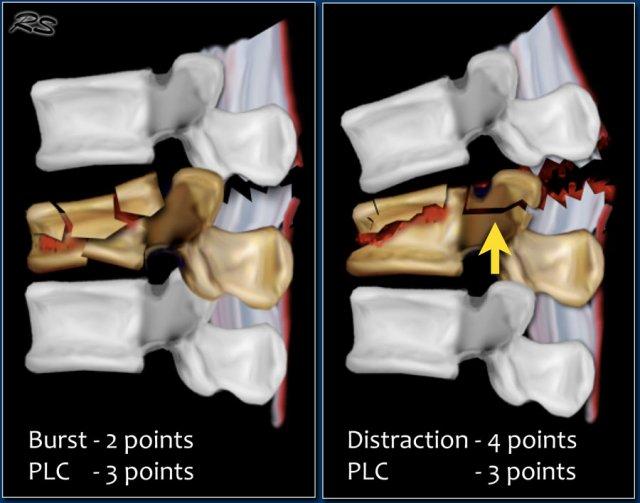

Gãy xương dạng nén được tính 1 điểm. Khi có thêm thành phần vỡ vụn (burst), sẽ được cộng thêm 1 điểm, tổng cộng là 2 điểm.

Hình thái tổn thương và PLC được tính điểm riêng biệt. Ví dụ, trong chấn thương tịnh tiến/xoay, PLC luôn bị tổn thương, tổng cộng là 3+3=6 điểm. Khi có lực giãn cách ở phía sau, PLC luôn bị tổn thương, tổng cộng là 4+3=7 điểm.

Trong một số trường hợp, có thể khó phân biệt giữa gãy vỡ vụn (burst) kèm đứt PLC và giãn cách kèm đứt PLC với gãy xương dạng nén ép (hình minh họa).

Bạn cần xác định vấn đề chính là gì: xẹp thân đốt sống hay giãn cách.

Vì trong cả hai trường hợp, điểm TLICS dựa trên hình ảnh đều cao, thường có chỉ định điều trị phẫu thuật.